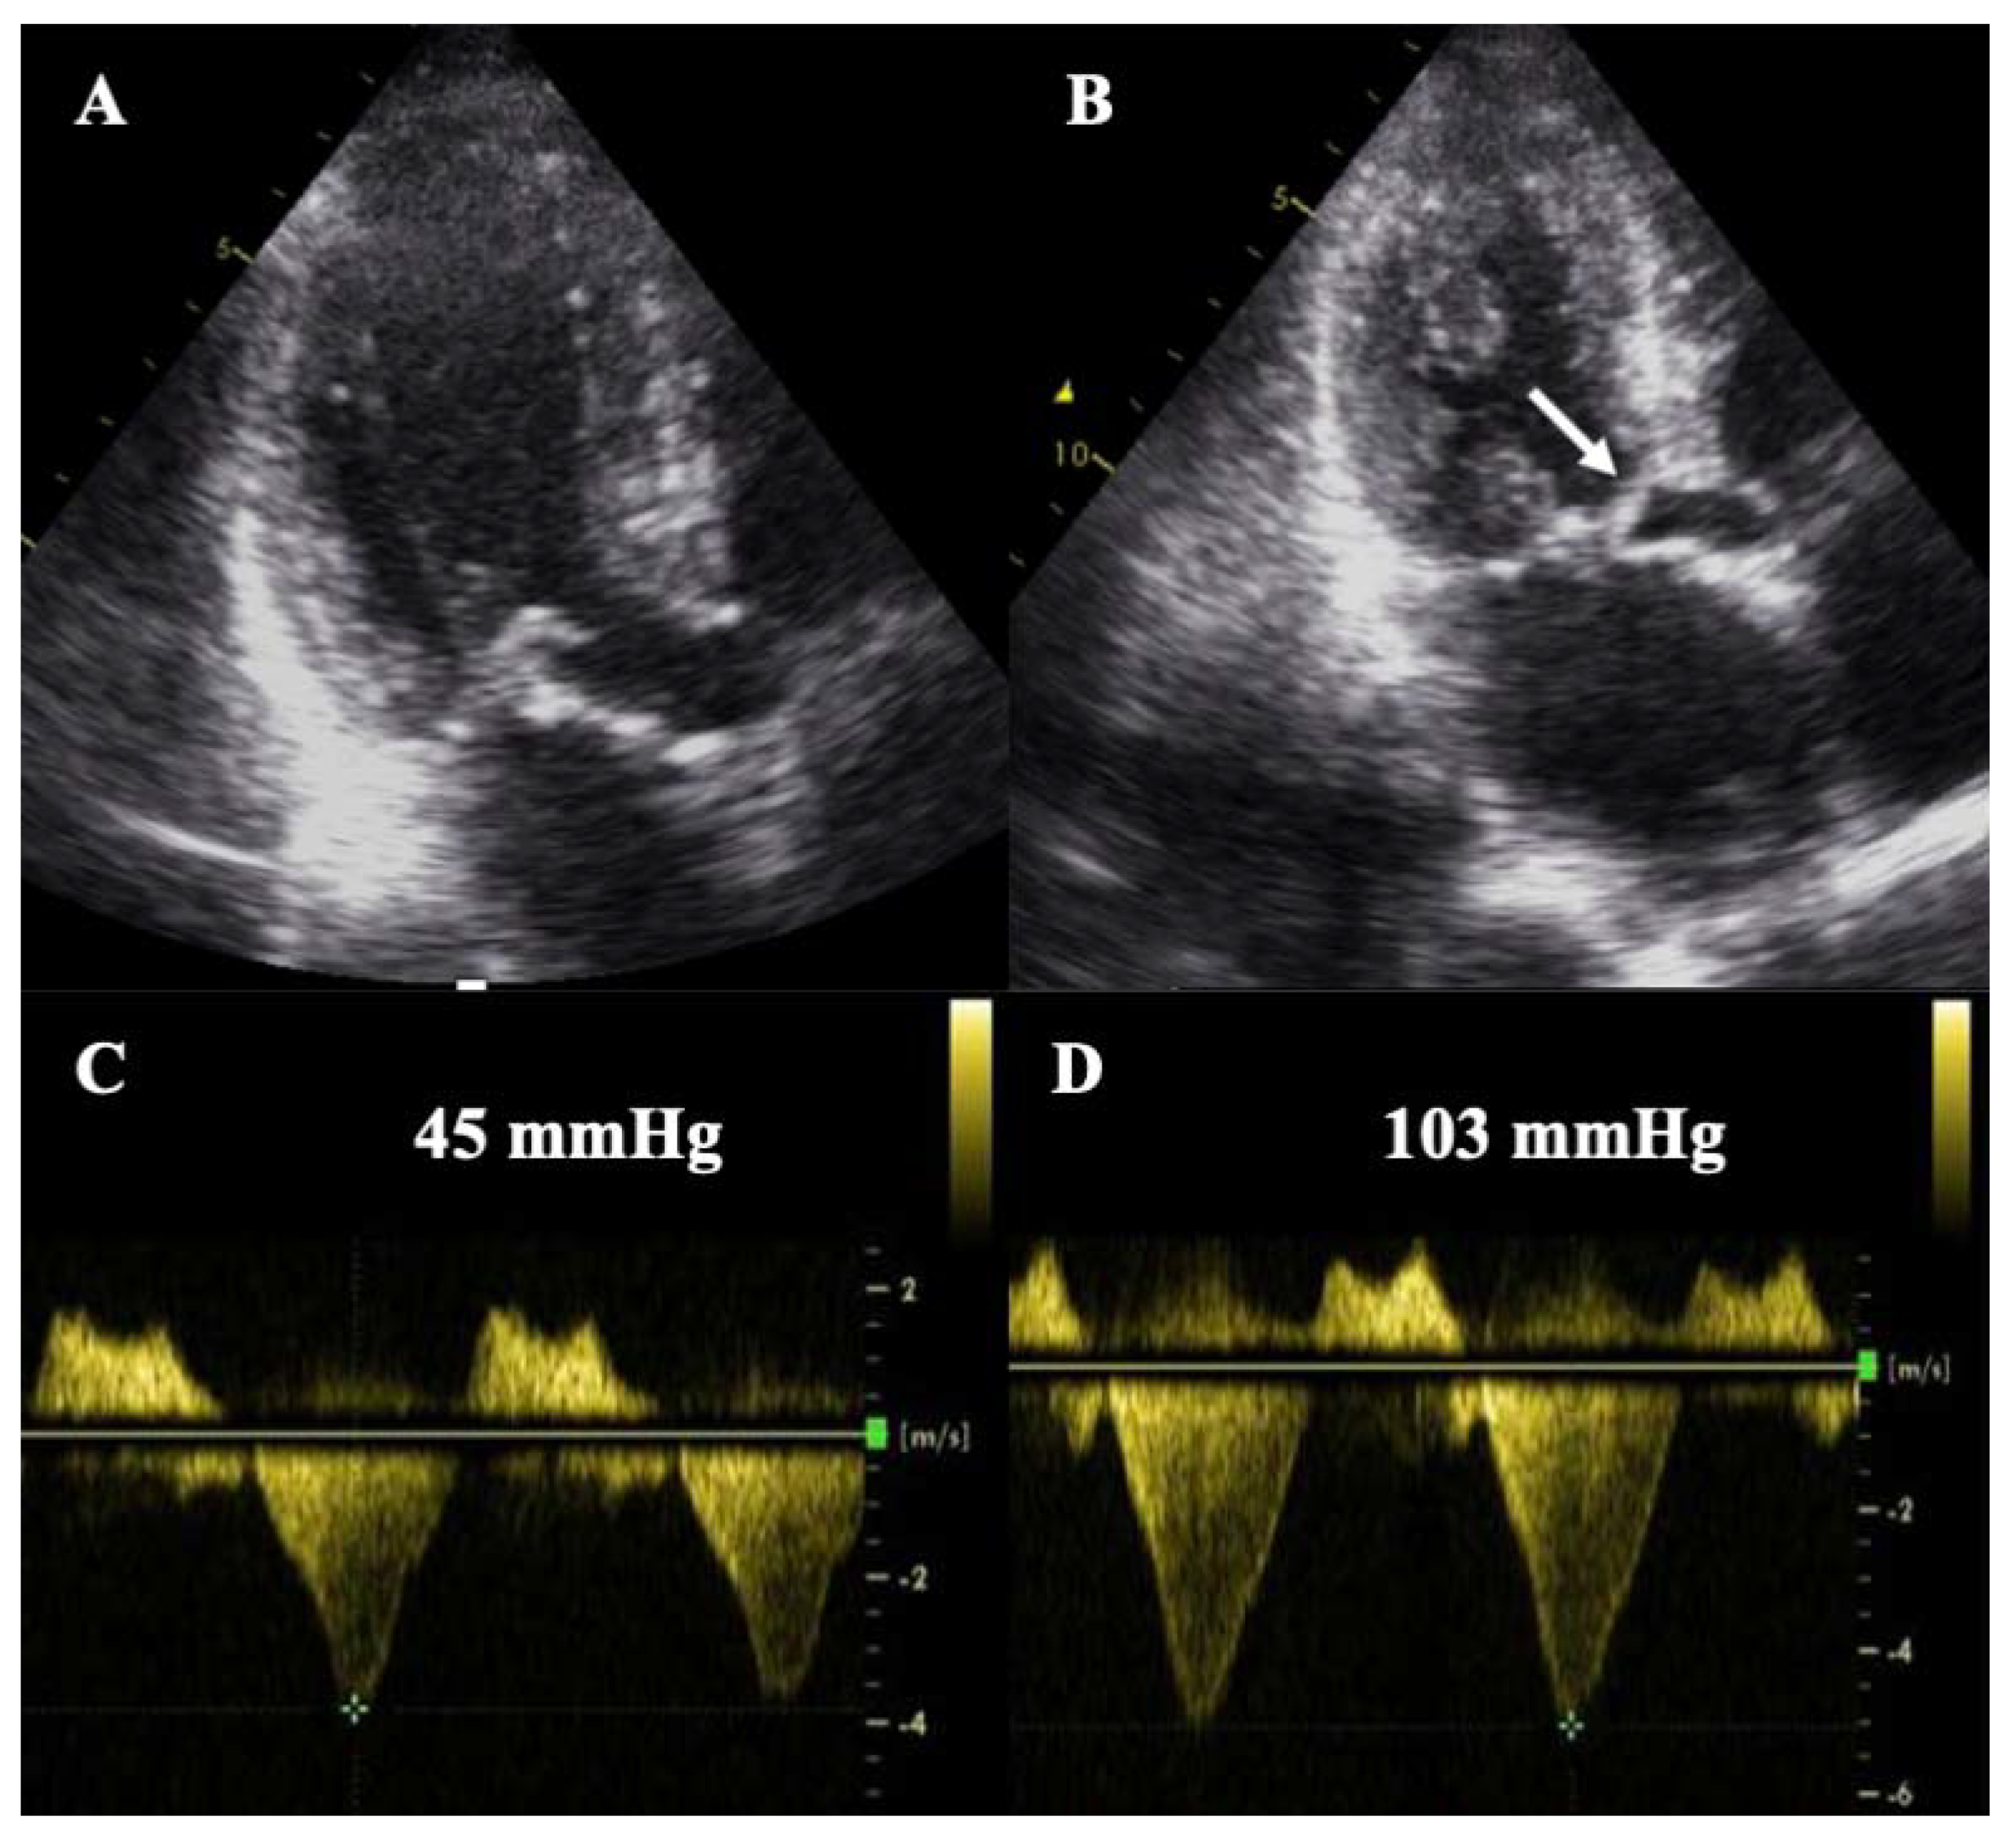

4.6. Endomyocardial Fibrosis